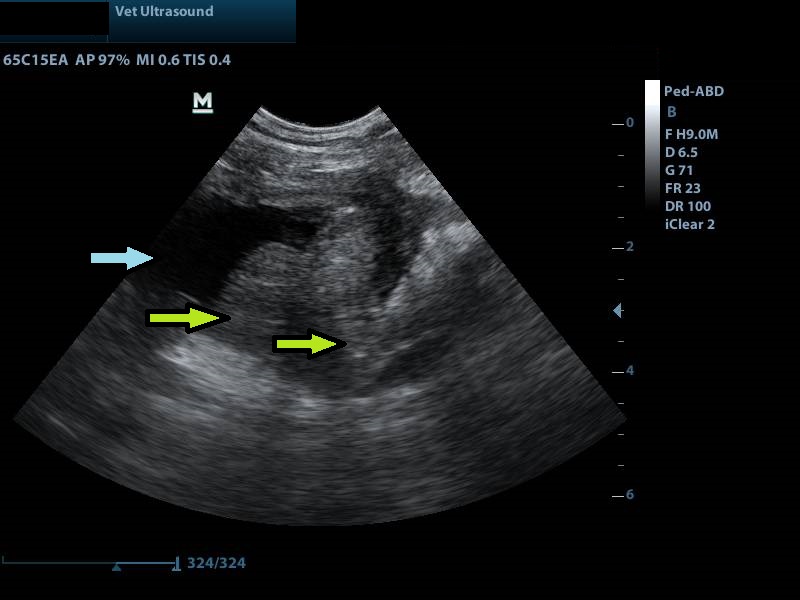

Ευρήματα: Στον υπέρηχο κοιλίας βρέθηκε νεοπλασία στο τρίγωνο της ουροδόχου κύστης το οποίο φαινόταν να διηθεί τους γύρω ιστούς. Το νεόπλασμα εμπόδιζε την έξοδο των ούρων μέσω του αριστερού ουρητήρα όπου είχε προκαλέσει υδρονέφρωση του σύστοιχου νεφρού. Ο δεξιός ουρητήρας και η νεφρική πύελος ήταν διατεταμένοι 7 mm (φυσιολογικό μέγεθος < 3 mm), χωρίς όμως να έχει επηρεαστεί η δομή του δεξιού νεφρού.

μπλε βέλος: υδρονέφρωση του αριστερού νεφρού

αριστερά της εικόνας ο προσανατολισμός του κέρσορα είναι κεφαλικά (ο θόλος της ουροδόχου κύστης και ουραία το νεόπλασμα)

μπλε βέλος: κοιλότητα της ουροδόχου κύστης γεμάτη με ούρα (μαύρο)

κίτρινο βέλος: η μάζα η οποία διηθεί και το τοίχωμα της ουροδόχου κύστης